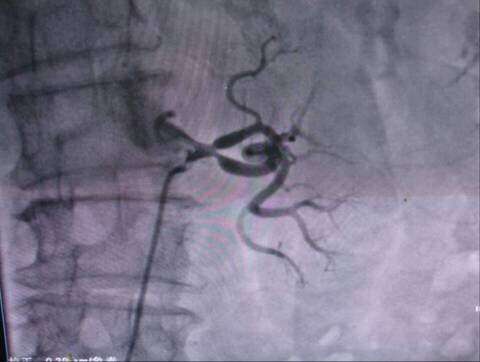

2003年任生博士开始关注干细胞的应用技术。当时干细胞的治疗只限于自体细胞培育和静脉滴入的简单的治疗技术,病种选择极少,当时有一个模糊的观念认为只要细胞进入体内,即游走到疾病的部位。在这种观念的影响下,干细胞应用的手法极其简单,治疗效果也很差。任博士敏锐的感觉到干细胞输入的途径是影响其治疗效果的重要因素。2009年在与项鹏博士的合作下,利用干细胞肝动脉介入技术成工地治疗了1例印度尼西亚肝硬化的病人,该病人治疗前重症腹水,转氨酶升高,重症黄疸肝功能3级。治疗后1周腹水消失,白蛋白增加,转氨酶下降。这里病例完成于2009年6月27日,是国内第一例异基因干细胞通过介入方式治疗成功的肝硬化病例,这是一个里程碑式的治疗案例,这例病人给任博士团队极大的信心。在接下来的2009―2013年期间,任博士利用他精湛的微创技术与干细胞技术结合,成功的治疗各种疾病的病人近千例。包括:重症肝病、尿毒症,糖尿病并发症、甲状腺功能低下,帕金森氏病,脑血管病后遗症,股骨头缺血性坏死、骨关节损伤、脊髓硬化症、银屑病、心梗后遗症、痛风性骨痛、风湿类风湿关节炎、硬皮病、红斑狼疮、血小板减少性紫癜,慢性阻塞性肺气肿、慢性胰腺炎等疾病。同时也在整形美容技术方面进行了拓展,成功地完成了生物支架细胞丰胸术、生物支架面部皮肤充填术,微针植入细胞因子肤质改善技术、微针植入生发术等等,并打造了数个第一:第一例异基因移植肾衰竭的介入治疗,第一例股骨头坏死得以基因介入治疗,第一例慢阻肺的异基因介入治疗等等。任生博士目前可用7种技术完成干细胞治疗的应用,包括动脉介入、静脉输注、经皮脏器穿刺注入、髓腔注入、肌层注入、真皮微针注入、穴位注射技术,目前是国内利用间充质干细胞治疗临床疾病类型最多的人,并且跨专业治疗最多的人,堪称国内第一人。特别是独创了中西医结合特色的(干细胞穴位注射疗法)和用于外伤修复及整形美容的(生物支架技术),这两项技术均申请了国家发明专利。另在干细胞的治疗过程中,不断完善干细胞的应用方案,如用量,疗程等。在这方面积累了大量的经验,为干细胞政策的开放后的广泛应用。做了大量和充足的准备。

印尼国家建筑设计院首席建筑设计师辛吉,2009年6月患严重肝硬化腹水来广州就医。经过多种方式治疗病情不见好转,在非常危急的情况下,我们向该患者提供了间充质干细胞,通过介入治疗技术将细胞输入到患者的肝脏,4天后患者的腹水完全消失,白蛋白上升,肝功各项指标明显恢复。至今病人依然健在。